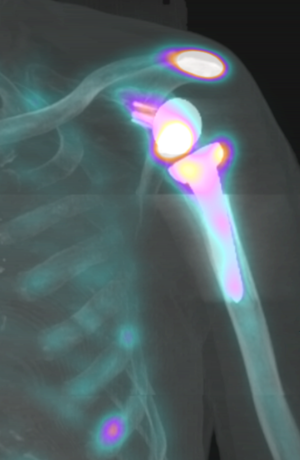

The use of positron emission tomography-computed tomography is helpful in diagnosis of non-displaced fractures.

SPECT CT of a left shoulder after a reverse shoulder arthroplasty. The patient developed pain 6 months after surgery. X-ray did not revealed fracture. SCPECT CT clearly demonstrated a hypersignal on the acromion.